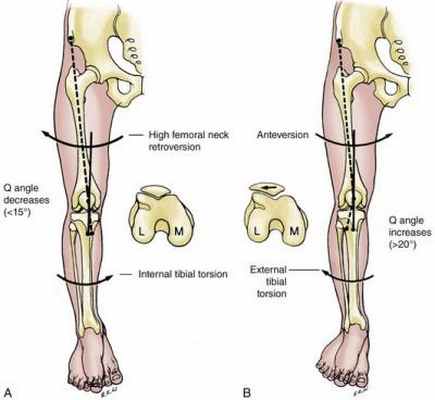

Угол Q

Направление и величина силы четырехглавой мышцы бедра оказывают большое влияние на биомеханику пателлофеморального сустава. Вектор силы квадрицепса ориентирован латерально по отношению к линии сустава. Это связано с большим поперечным сечением и потенциалом латеральной головки квадрицепса. Поскольку существует связь между патологией надколенника и его чрезмерным перемещением в латеральном направлении, оценка латерального натяжения квадрицепса по отношению к надколеннику является важным клиническим измерением. Оно называется «угол квадрицепса» или «угол Q». Впервые угол квадрицепса был описан Братстромом (Brattstrom).

Угол Q определяется:

Угол Q определяется линией, идущей от передней верхней подвздошной ости к центру надколенника, и от центра надколенника к бугристости большеберцовой кости. Угол Q можно измерять в положении лежа или стоя. Последний вариант предпочтительнее, поскольку в этом состоянии коленный сустав находится большую часть времени.

Нормальным углом Q у здоровых людей от 18 до 35 лет считается угол в 13.5 ± 4.5°.

Угол Q у женщин больше на 4.6°, чем у мужчин, из-за более широкого таза, большей феморальной антеверсии и вальгусного угла колена.

Факторы, влияющие на формирование угла Q

Увеличение угла Q связано с такими факторами, как:

Феморальная антеверсия

Наружная ротация большеберцовой кости

Латеральное смещение бугристости большеберцовой кости

Genu valgum: отклонение бедренной кости + смещение вектора силы квадрицепса

Клиническое значение

Понимание нормального анатомического и биомеханического функционирования пателлофеморального сустава необходимо для правильной оценки состояния колена. Сформированный вектором совместного натяжения квадрицепса и сухожилия надколенника, угол Q представляется важным, поскольку позволяет измерить латеральное воздействие на надколенник.

Предполагается, что любое увеличение угла Q повышает латеральное воздействие на надколенник.

Это может быть опасным, поскольку повышение латеральной нагрузки может увеличивать давление надколенника на наружный край межмыщелковой борозды бедренной кости.

При наличии достаточной латеральной силы может происходить подвывих или смещение надколенника относительно межмыщелковой борозды (когда квадрицепс приводится в действие при разогнутом колене). Также предполагается, что патологическая величина угла Q может влиять на нейромышечную реакцию и скорость восстановления четырехглавой мышцы бедра.